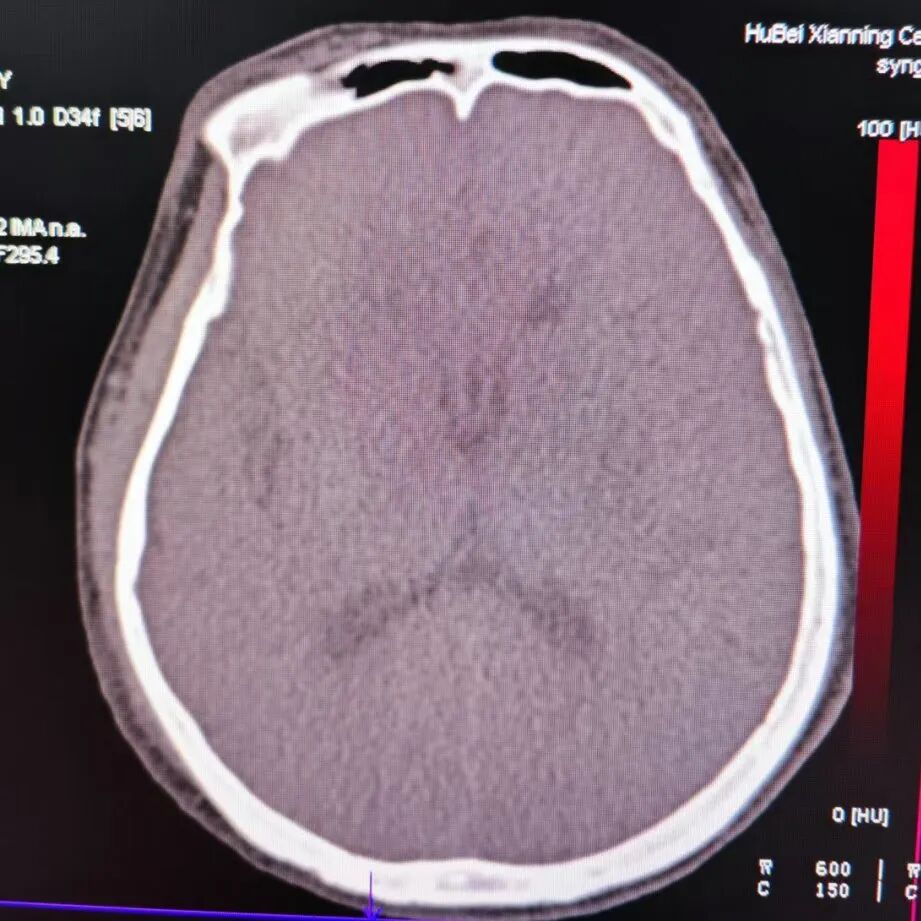

术后影像

术后CT提示基底节区高密度灶。

动脉长鞘怎么置入有励可说|Locaste 088励楷长鞘及Tarvos微导丝在左侧大脑中动脉闭塞取栓术中的应用_https://www.jmylbn.com_新闻资讯_第22张

动脉长鞘怎么置入有励可说|Locaste 088励楷长鞘及Tarvos微导丝在左侧大脑中动脉闭塞取栓术中的应用_https://www.jmylbn.com_新闻资讯_第23张

去碘后考虑造影剂外渗。

动脉长鞘怎么置入有励可说|Locaste 088励楷长鞘及Tarvos微导丝在左侧大脑中动脉闭塞取栓术中的应用_https://www.jmylbn.com_新闻资讯_第24张

动脉长鞘怎么置入有励可说|Locaste 088励楷长鞘及Tarvos微导丝在左侧大脑中动脉闭塞取栓术中的应用_https://www.jmylbn.com_新闻资讯_第25张